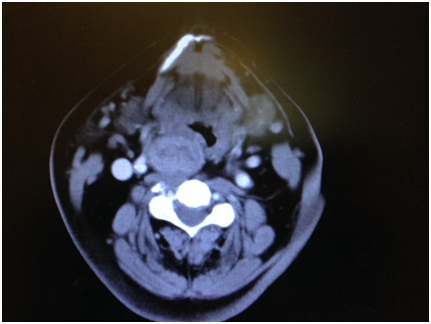

Incidentally, during examination a large thyroid mass was noted. A CT scan of the neck revealed a large thyroid mass extending to suprahyoid area on the right sides. Given the size of the thyroid it was decided to do a right hemi-thyroidectomy. Patient’s vertiginous symptoms completely resolved following thyroidectomy. Patient was followed up for 3years with no recurrence of her symptoms.

Based on the case report we presented, it is recommended that patients seen with symptoms like those of benign paroxysmal positional vertigo who do not show improvement after undergoing the particle repositioning maneuver should have imaging studies of neck and brain. Measuring artery flow in neutral and neck rotated position using Doppler ultrasonography and comparing the results may be diagnostic in patients with vertigo due to vascular compression. However, the procedure is not practical because it is difficult to scan the distal part of the artery during rotation.3 CT angiography may be considered an alternative option (Figure 1–3).

Figure 1 CT scan soft tissue neck showing enlarged thyroid displacing carotid artery on the right side.